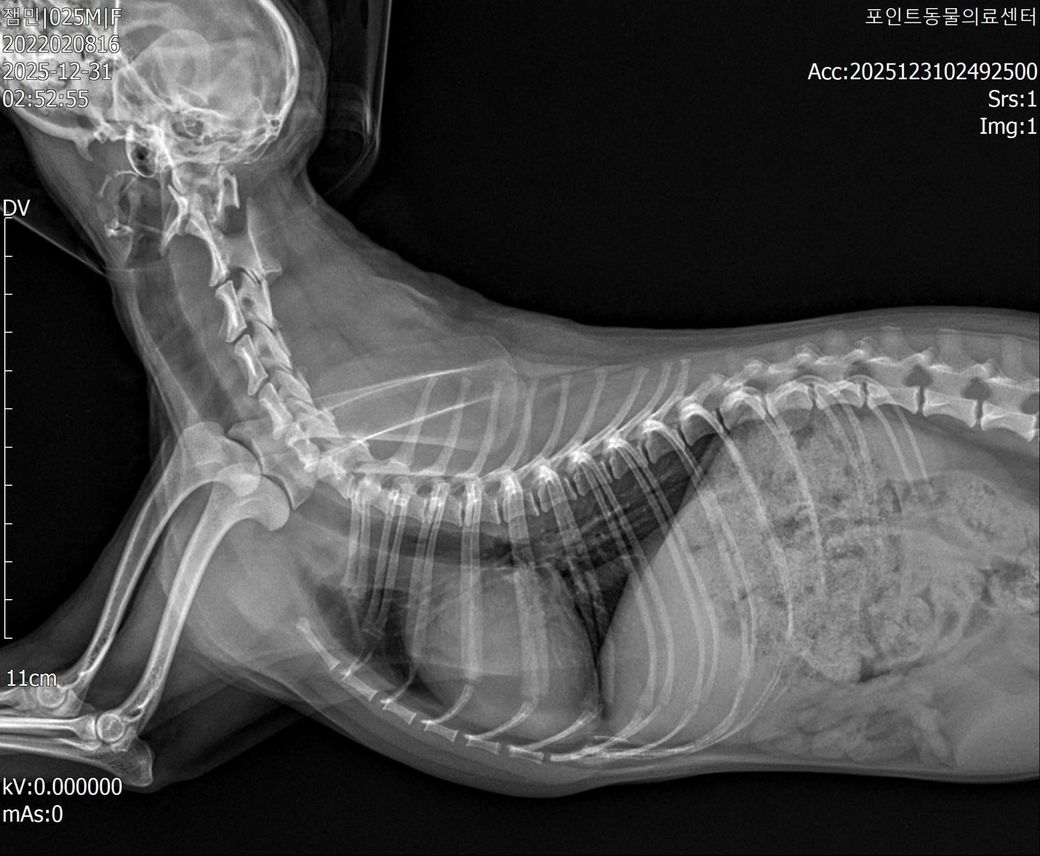

척수증, 척수연화증 판정 받았습니다만, 제가 저희 아이 CT사진을 확인했을때 환축추아(AAI)로도 의심해볼 수 있을거같은데 도움이 필요합니다,,

■ 반려동물 질환 : 척수증, 척수연화증, 환축추아(AAI)

현재까지의 내용입니다, 현재도 고개만 움직일 수 있으며, 팔과 다리는 스스로 움직일 수 없는 상황입니다. (현재 스테로이드 치료 4일차) 다만 제가 검색을 계속 하다보니 저희 강아지 CT 사진을 보아 환축추아(AAI)로도 의심이 되는데 가능성이 있는지 확인 가능하신 분 있으시면 확인좀 부탁드립니다 사진 첨부드립니다..

방사선 사진상 환축추불안(AAI)가능성은 낮아 보입니다. 물론 stress view 등 진단을 위한 standard view가 아니기 때문에 이는 추정이며 환자를 직접 본 주치의 판단이 가장 정확합니다.